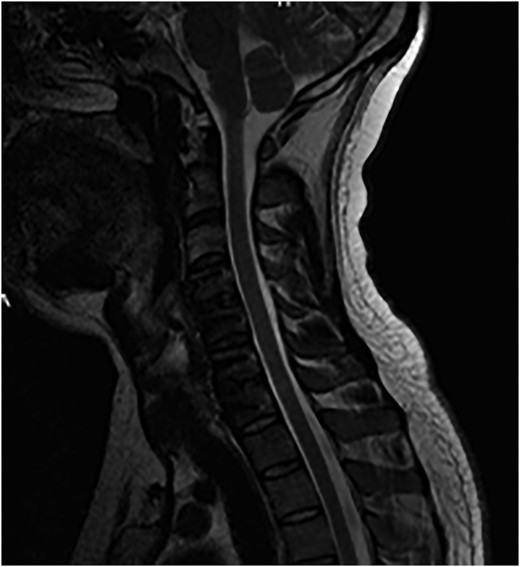

The MR of the C-Spine revealed C4/C5 subluxation (flexion–distraction injury) with total rupture of posterior ligamentous complex including PLL with acute traumatic disc herniation at C4/C5 level causing significant narrowing of the spinal canal at the level but no evidence of cord signal changes. Partial injury to Nuchal ligament with an acute injury to C6/C7 disc with posterior annular tear with disc extrusion, almost sequestration behind vertebral body of C7 towards left C7/T1 neural foramen, was also noted (Figs 3–5).

Sagittal T2-weighted MRI images showing a disc herniation at C4/5 and a non-contiguous disc extrusion at C/67 behind the vertebral body of C7.